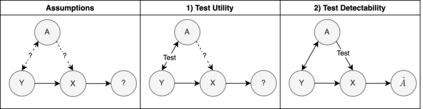

To safely deploy deep learning-based computer vision models for computer-aided detection and diagnosis, we must ensure that they are robust and reliable. Towards that goal, algorithmic auditing has received substantial attention. To guide their audit procedures, existing methods rely on heuristic approaches or high-level objectives (e.g., non-discrimination in regards to protected attributes, such as sex, gender, or race). However, algorithms may show bias with respect to various attributes beyond the more obvious ones, and integrity issues related to these more subtle attributes can have serious consequences. To enable the generation of actionable, data-driven hypotheses which identify specific dataset attributes likely to induce model bias, we contribute a first technique for the rigorous, quantitative screening of medical image datasets. Drawing from literature in the causal inference and information theory domains, our procedure decomposes the risks associated with dataset attributes in terms of their detectability and utility (defined as the amount of information knowing the attribute gives about a task label). To demonstrate the effectiveness and sensitivity of our method, we develop a variety of datasets with synthetically inserted artifacts with different degrees of association to the target label that allow evaluation of inherited model biases via comparison of performance against true counterfactual examples. Using these datasets and results from hundreds of trained models, we show our screening method reliably identifies nearly imperceptible bias-inducing artifacts. Lastly, we apply our method to the natural attributes of a popular skin-lesion dataset and demonstrate its success. Our approach provides a means to perform more systematic algorithmic audits and guide future data collection efforts in pursuit of safer and more reliable models.